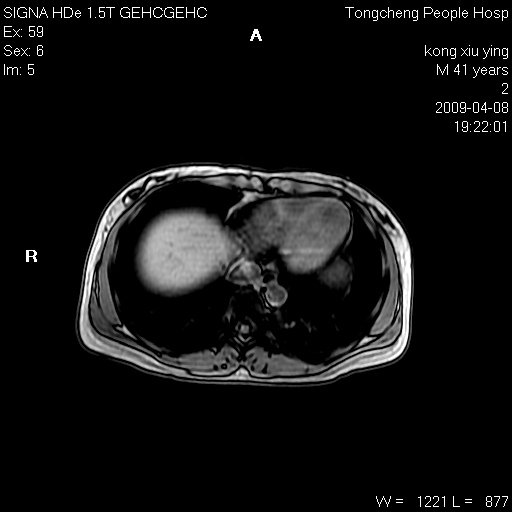

标题: CL1008:【经典】胆囊石榴籽样结石。 [打印本页]

标题: CL1008:【经典】胆囊石榴籽样结石。

女,41岁。健康体检——彩超提示:胆囊显示不清。平素健康,无不适感。

腹部mr扫描及mrcp,图像如下:

胆囊石榴籽样结石。